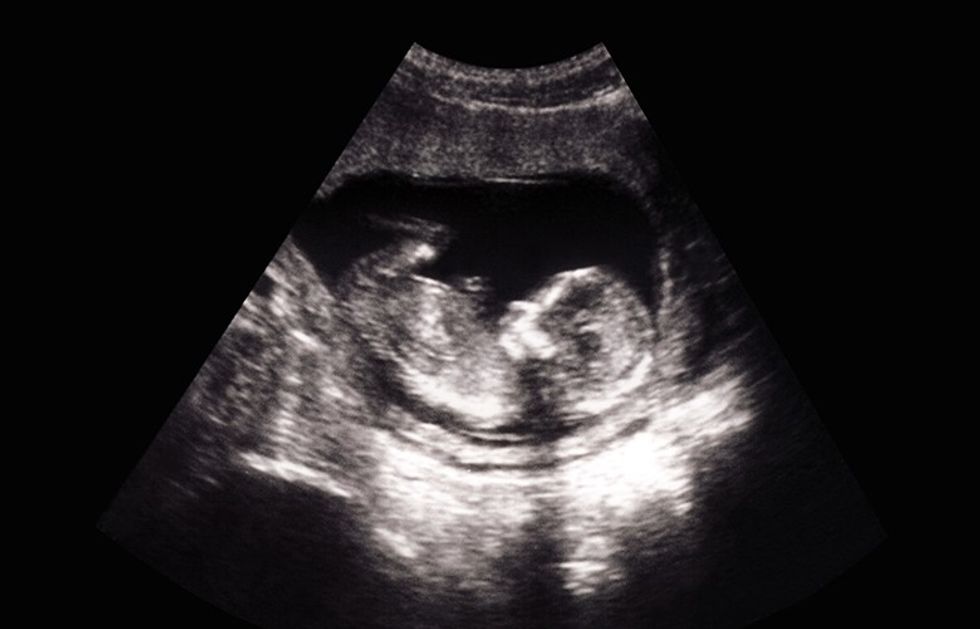

Ka ardhur java e tridhjetepestë e shtatzënisë dhe ja ndryshimet që mund të prisni në të kur bëhet fjalë për beben, por edhe për ju.

Tani bebja është rreth 44 cm e gjatë dhe peshon rreth 2.500 gram. Veshkat tani janë zhvilluar plotësisht dhe mëlçia mund të përpunojë disa mbetje materiale. Mushkëritë ndoshta janë pjekur plotësisht. Pjesa më e madhe e zhvillimit fizik bazë ka përfunduar dhe në javët e ardhshme bebja do të shtojë peshë (rreth 200-250 gram në javë).